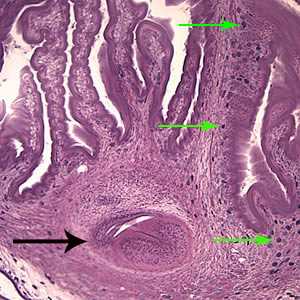

This was a case of cysticercosis caused by the larval stage of Taenia solium. Diagnostic features were:

- a single protoscolex (yellow circle, Figure A) visible within the bladder wall (blue arrows, Figure A). Racemose cysticerci are characterized by proliferating, lobulated cysts without a scolex which are usually found in the ventricular system and subarachnoid space, and, rarely, in the cerebral parenchyma.

- the extensive folding of the spiral canal and one sucker of the protoscolex (black arrow, Figure B).

- the presence of calcareous corpuscles (green arrows, Figure B).

Figure A

Figure B